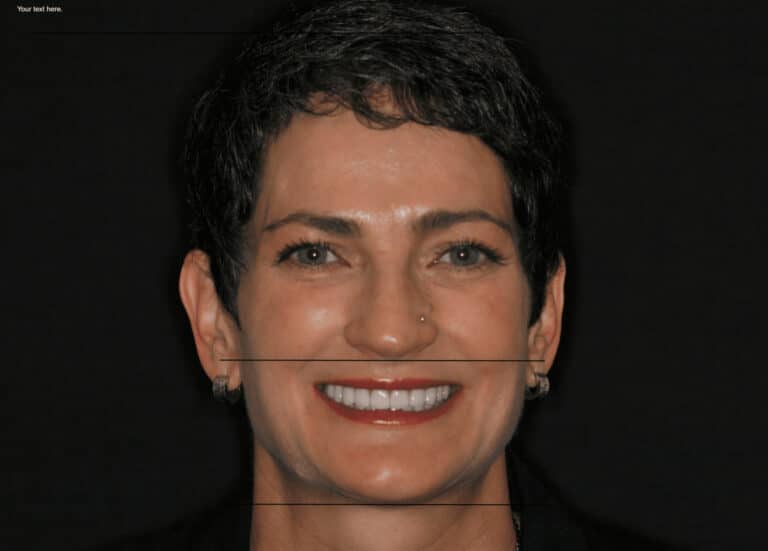

These photos show a lady who was unhappy that her teeth did not show when smiling and her narrow smile. Additionally, she had TMJ symptoms and and deep overbite with a collapsed face and weak chin. Dr. Konig corrected her jaw alignment and found her correct physiologic bite. End

Individual results may vary.This case portrays a lovely lady with worn teeth, overbite, and TMJ Pain. Finding the correct physiologic bite position for the facial muscles, joints, and face allowed her to have a beautiful smile, no more overbite, and a more beautiful profile!

Overbite, Weak Chin, TMJ PainOverbite correction non surgically

Overbite/UnderbiteIn this particular case, the lower 1/3 of the face was lengthened which also moved the lower jaw forward eliminating the retruded chin often found in overbite patients. Notice the tremendous improvement in facial esthetics, profile, and muscle tone not to mention the outstanding smile!

Non-surgical Overbite Correction and TMJ Pain TreatmentThis case shows how an overbite can be corrected conservatively to create a beautiful smile and relieve TMJ pain. Not only did this relieve pain it changed the patients lower 1/3 of her face which had collapsed due to the overbite. The retruded chin and aging appearance was corrected

Non-surgical Overbite Correction and TMJ Pain Relief